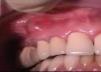

Absceso gingival (fig. 3): doloroso, localizado en la encía marginal e interdental, generalmente asociado al impacto de cuerpos extraños.